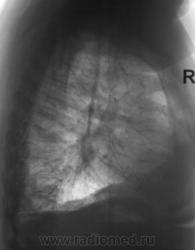

Пол пациента: Мужской пол Тип патологии: Другое Область исследования: Грудная клетка и верхние дыхательные пути Методы исследования: Rg При расшифровке фицровых флюорограмм пациент взят на контроль. Жалоб нет. Пациент преклонного возраста. Ваше мнение коллеги? https://radiomed.ru/sites/default/files/styles/case_slider_image/public/2.U.Kontrol.JPG?itok=D_X_PWlr https://radiomed.ru/sites/default/files/styles/case_slider_image/public/3.U.Kontrol.JPG?itok=WUYf75C2 https://radiomed.ru/sites/default/files/styles/case_slider_image/public/4.U.Kontrol.JPG?itok=Qim3Ihlu ID:29 Чт, 07/01/2010 - 15:39 #1 Анатолий Владим... Не на сайте Был на сайте: 8 лет 3 месяцев назад Зарегистрирован: 16.10.2009 - 21:16 Публикации: 1941 Похоже на ателектаз десятого сегмента справа. Ср, 13/01/2010 - 20:55 #2 Ольга Дмитриевна Не на сайте Был на сайте: 16 лет 2 месяцев назад Зарегистрирован: 13.01.2010 - 16:55 Публикации: 168 Средней доли тоже нет. Центральный рак? КТ бы надо. Красота - гормон карьерного роста! Ср, 10/08/2011 - 19:38 #3 Nikolas Не на сайте Был на сайте: 1 месяц 3 недели назад Зарегистрирован: 21.12.2010 - 20:37 Публикации: 4560 Уважаемый Валентин Львович! Что же у больного все-таки оказалось после дообследования? С уважением Nikolas Пт, 12/08/2011 - 22:11 #4 Катенёв Валенти... Не на сайте Был на сайте: 7 лет 5 месяцев назад Зарегистрирован: 22.03.2008 - 22:15 Публикации: 54876 Пациентку пролечили в течение 2-х недель в Т.О., сделали "контроль", написали возрастную норму.

Похоже на ателектаз десятого сегмента справа.

Средней доли тоже нет. Центральный рак? КТ бы надо.

Пациентку пролечили в течение 2-х недель в Т.О., сделали "контроль", написали возрастную норму.